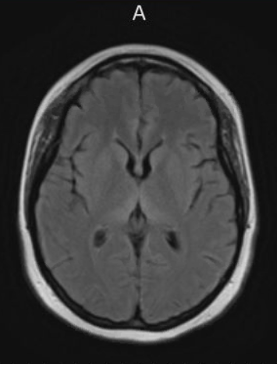

Workup should include measuring a serum thiamine level in addition to a magnetic resonance imaging (MRI) of the brain with and without contrast with concurrent neurology consultation. MRI will traditionally show T2 hyperintense signal abnormalities involving the bilateral posterior medial thalami symmetrically with increased signal in the periaqueductal area and tectal plate (Figure). Signal abnormalities in the mamillary bodies may present but are less common.3,4

The patient’s serum thiamine level was 70. The findings of an MRI were consistent with Wernicke’s encephalopathy. The patient was hospitalized for 8 days with IV thiamine repletion and subsequently discharged on a daily oral thiamine regimen. At discharge, the patient showed significant improvement in her neurologic function, with mild fine motor deficits and steady gait. Repeat MRI prior to discharge showed improvement in signal abnormalities. In this case, the patient was fortunate in that she showed remarkable recovery. Vitamin repletion does not always reverse the clinical deficits.Learning points